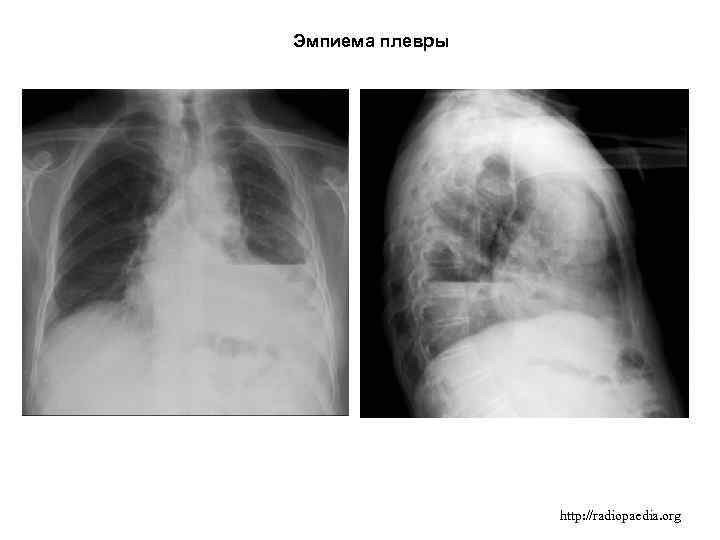

Диагностика плеврального выпота: что нужно знать